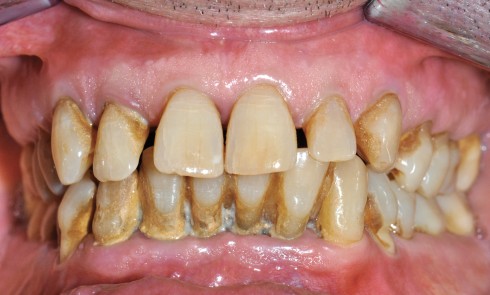

Article réservé à nos abonnés Un traitement parodontal simple mais efficace

Il arrive que des affections parodontales restent ignorées par l’omnipraticien, souvent parce que les signes d’appel sont mal appréhendés, voire...